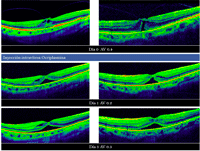

Cierre espontáneo

Es posible observar el cierre espontáneo en un 50% de las tracciones vitreomaculares con agujeros maculares incompletos (grado I en la antigua clasificación por OCT)

11 (

Figura 9), pero sólo se consigue la resolución espontánea en un 2% a un 4% de los agujeros de grosor completo (grados 2-4 de la antigua clasificación)

11,12.

Figura 9. Cierre espontáneo de agujero macular de grosor incompleto y tracción vitreomacular. Se objetiva un agujero que implica las capas externas de la retina, aunque no llega a ser completo en las capas más internas. Se produce un cierre espontáneo a lo largo de 3 meses de seguimiento. El paciente conservaba agudeza visual, pero refería metamorfopsias y leve escotoma central que se desaparecieron tras la resolución del cuadro.